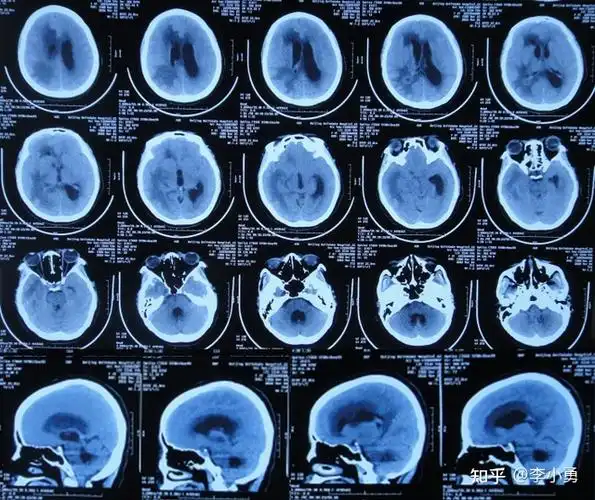

先天心脏病并发脑脓肿和脑积水,反复头痛恶心发热视力模糊不认识人